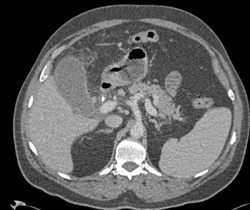

Gallstones and Mass in Gallbladder